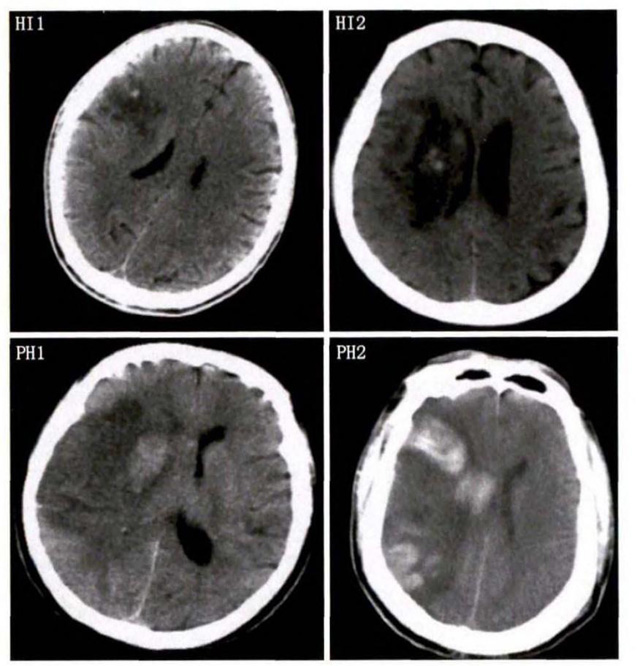

中、老年病患,有動脈粥樣硬化及高血壓病等腦卒中的危險(xiǎn)因素,發(fā)病結(jié)合神經(jīng)系統(tǒng)癥狀和體征,應(yīng)當(dāng)考慮急性腦梗死的可能。再經(jīng)腦CT/MRI發(fā)現(xiàn)梗死灶,或排除腦出血、炎癥性疾病等,診斷即可確定。腦梗死有時(shí)頗似小量腦出血的臨床表現(xiàn)。腦栓塞在任何年齡都可以有發(fā)病的風(fēng)險(xiǎn),可以在幾秒到幾分鐘達(dá)到頂峰。會有偏癱不能說話等局部神經(jīng)功能損壞。栓子來源很種,可能是冠心病、心肌梗塞、心內(nèi)膜炎等。合并心房纖顫,結(jié)合其他臟器官的支持診斷,CT跟磁共振都可以檢查確定栓塞位置數(shù)量還有是不是有伴發(fā)出血等問題。可以幫助診斷。

中老年有高血壓糖尿病發(fā)病病史,起病神經(jīng)功能缺損癥狀,臨床表現(xiàn)為腔隙綜合征,即可初步診斷本病。如果CT或磁共振證實(shí)有與神經(jīng)功能缺失一致的腦部腔隙病灶, 符合大腦半球或腦干深部的小穿通動脈病變,即可明確診斷。少數(shù)患者隱匿起病,無明顯臨床癥狀,在影像學(xué)檢查時(shí)發(fā)現(xiàn)。